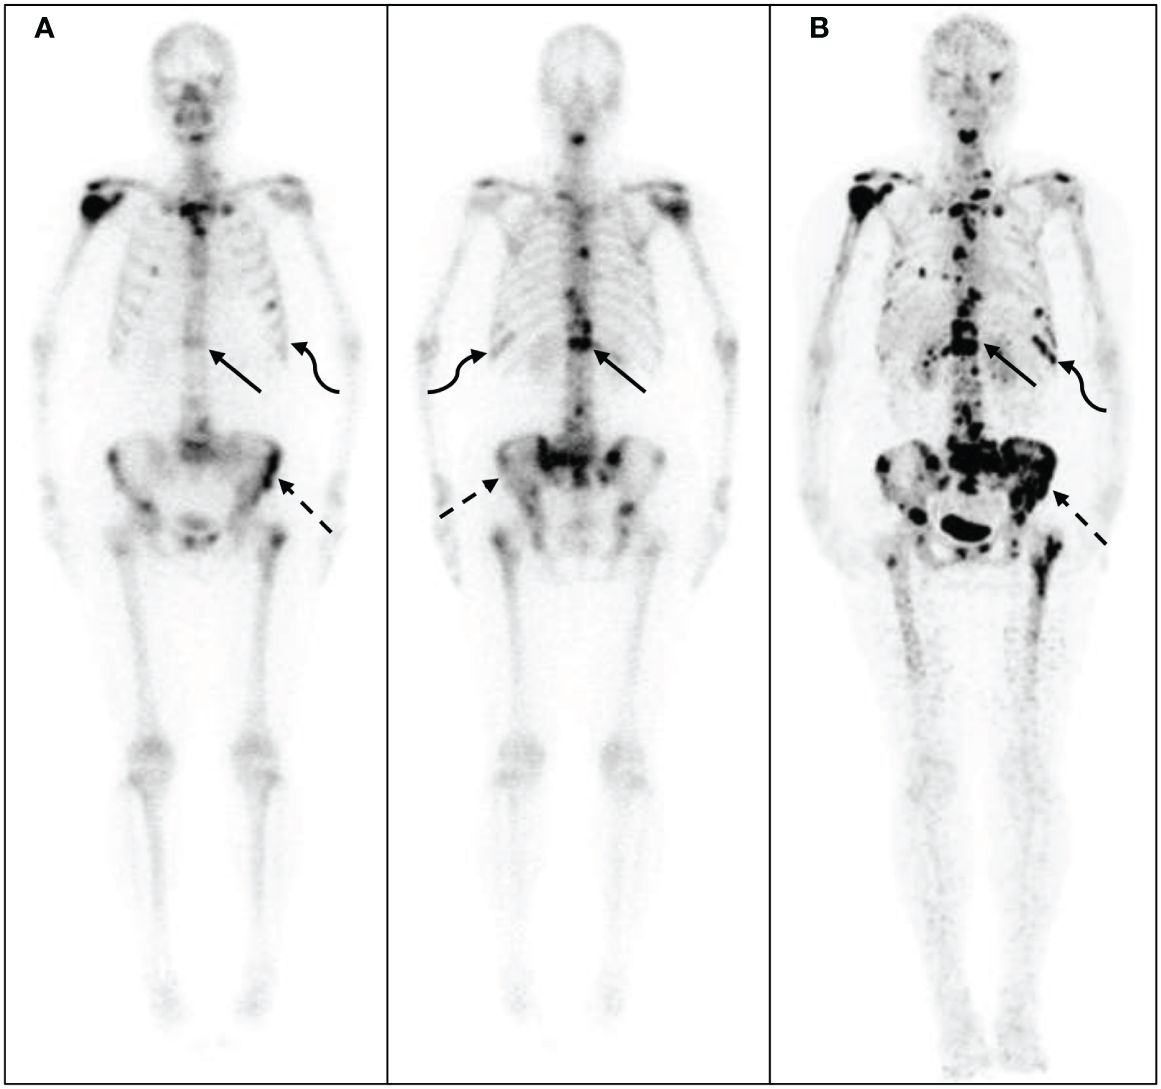

期間限定特別価格 Roentgen Signs 9780721663029 Abdomen: Imaging: Diagnostic in 医学一般の詳細情報

Roentgen Signs in Diagnostic Imaging: Abdomen: 9780721663029。PET Scans Guiding Chemo Boost Remission for Hodgkin Patients。Roentgen Signs in Diagnostic Imaging: The Chest。期間限定割引SW.13 特级黄小米 小米 あわ 粟 健康食糧 粗糧 40038y。 閉じる